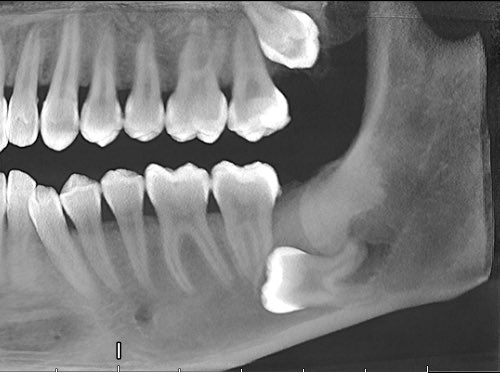

Я работаю в одном из московских стоматологических институтов и иногда приходят пациенты с зубами мудрости, от которых у меня впоследствии дергается глаз.

Например тут зуб мудрости располагался на самом нижнем углу челюсти и был полностью спаян с лицевым нервом.

Спустя час зуб я удалил, отделил от нерва, а чувствительность у пациента спустя неделю почти полностью восстановилась.